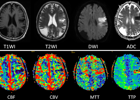

近期,影像诊断中心通过新开展磁共振脑灌注成像(PWI)技术,陆续为十多例脑疾患者进行检查,效果十分显著。据悉,与普通的磁共振检查相比,PWI技术能更加清晰准确显示疾患所在,为下一步治疗提供具体参数。 近日,72岁高龄男性患者因无明显诱因出现不能言语、右侧肢体乏力、不能站立及行走等症状,休息后未见缓解,遂至...2022-07-15